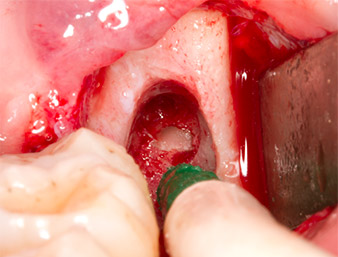

El tejido situado por encima del resto radicular no se había osificado por completo y constaba en su mayor parte de un tejido granulado con alteraciones inflamatorias (figura 4).

Con el fin de obtener material autógeno para el tratamiento posterior de la herida, se utilizó un inserto piezoquirúrgico (Piezomed B5) para obtener virutas de hueso sano del entorno del resto radicular (figura 5).

tejido granulado

Imagen 4: Dos ganchos de Langenbeck y un raspador según Prichard exponen el campo quirúrgico. Se distingue un tejido granulado de la primera osteotomía que no ha cicatrizado en su totalidad.